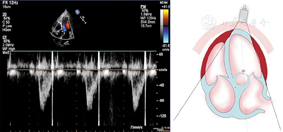

(1)胸骨旁左心室长轴切面(图1图2图3)

胸骨旁左心室长轴切面引导2a区M型超声心动图,显示收缩末期和舒张末期室间隔厚度、左心室内径和左心室后壁厚度测量方法